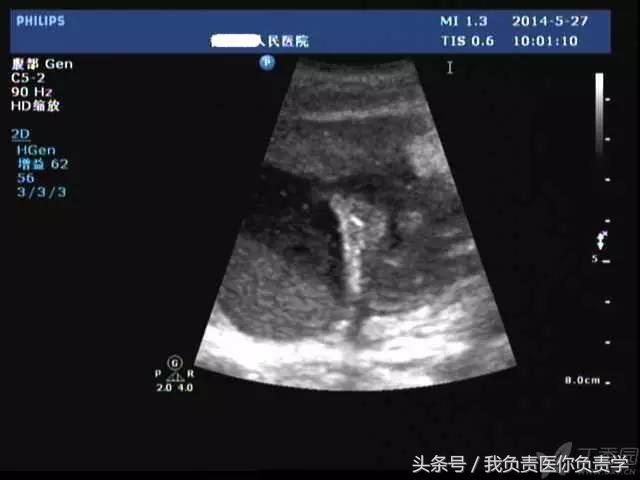

典型病例 1

患者男,64岁,因右上腹疼痛半月余就诊。查体发现右上腹部轻压痛,无发热。超声检查所见如下:

图2示于胆囊外侧可见一局限性囊性无回声区